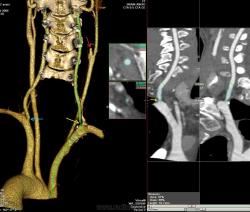

Наблюдение Nela.

Мужчина, 62 года. Перенес ишемический инсульт в бассейне правой средней мозговой артерии.

На КТ-ангиографии выявлена окклюзия правой внутренней сонной артерии в области развилки в виде паламени свечи (красная стрелка), стеноз высокой степени в устье правой вертебральной артерии (желтая стрелка), небольшой перегиб в устье левой вертебральной артерии (голубая стрелка).